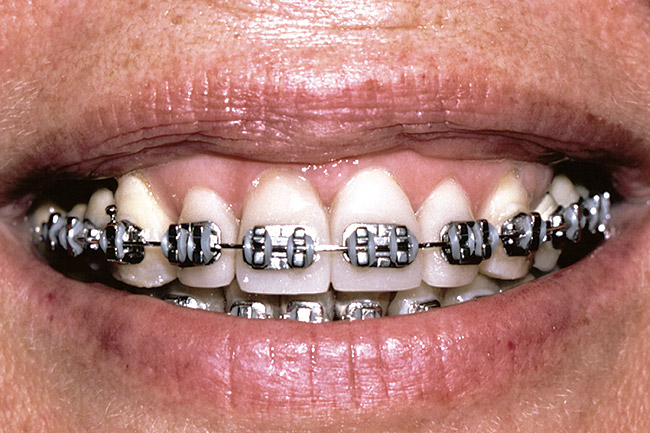

Figure 3  Orthodontics has intruded the incisors to create space to bond them to a pleasing length.

Figure 3

Again, the starting point is a set of mounted models, an orthodontic set-up, and a diagnostic wax-up. The worn teeth are cut from the set-up and waxed to normal length. They are then replaced in the set-up and become the guide for treatment. Whether they are lengthened before or during orthodontics depends upon whether space exists to lengthen them prior to orthodontics. If it does, they can be temporarily restored prior to treatment. If not, the orthodontist must first create space, then de-bracket the worn teeth and send the patient to the restorative dentist for temporary restoration. The brackets are then replaced and the orthodontics completed. The need to open space prior to correcting tooth length is common when utilizing orthodontics to intrude severely worn and over-erupted maxillary or mandibular incisors (Figure 2, Figure 3, Figure 4 and Figure 5).